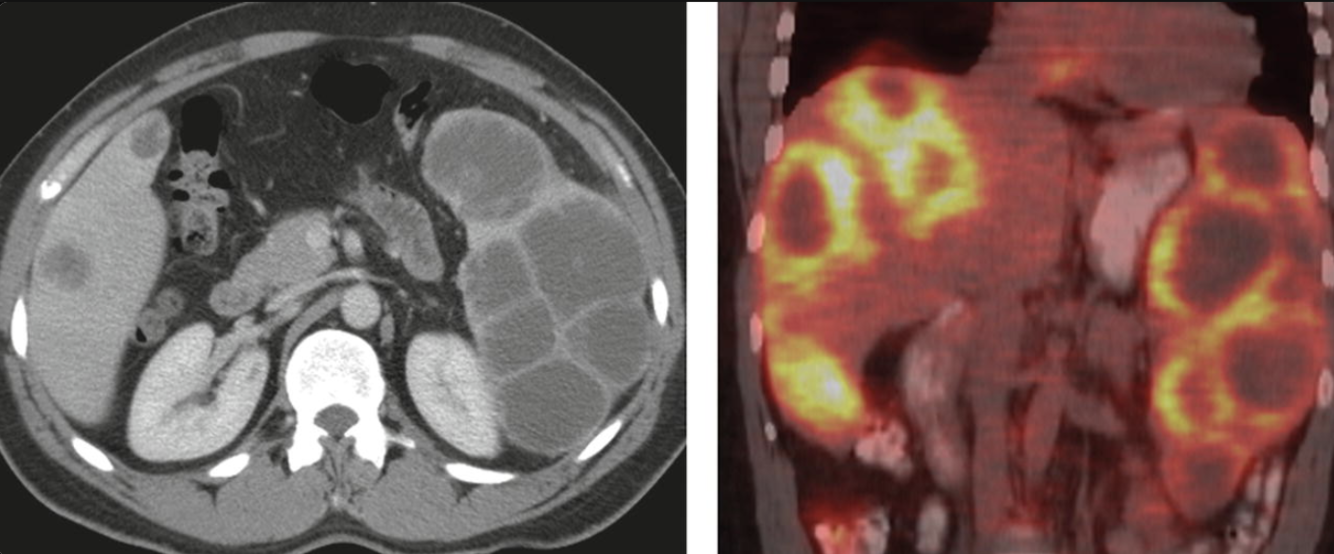

Name the most common met to the pancreas

RCC!